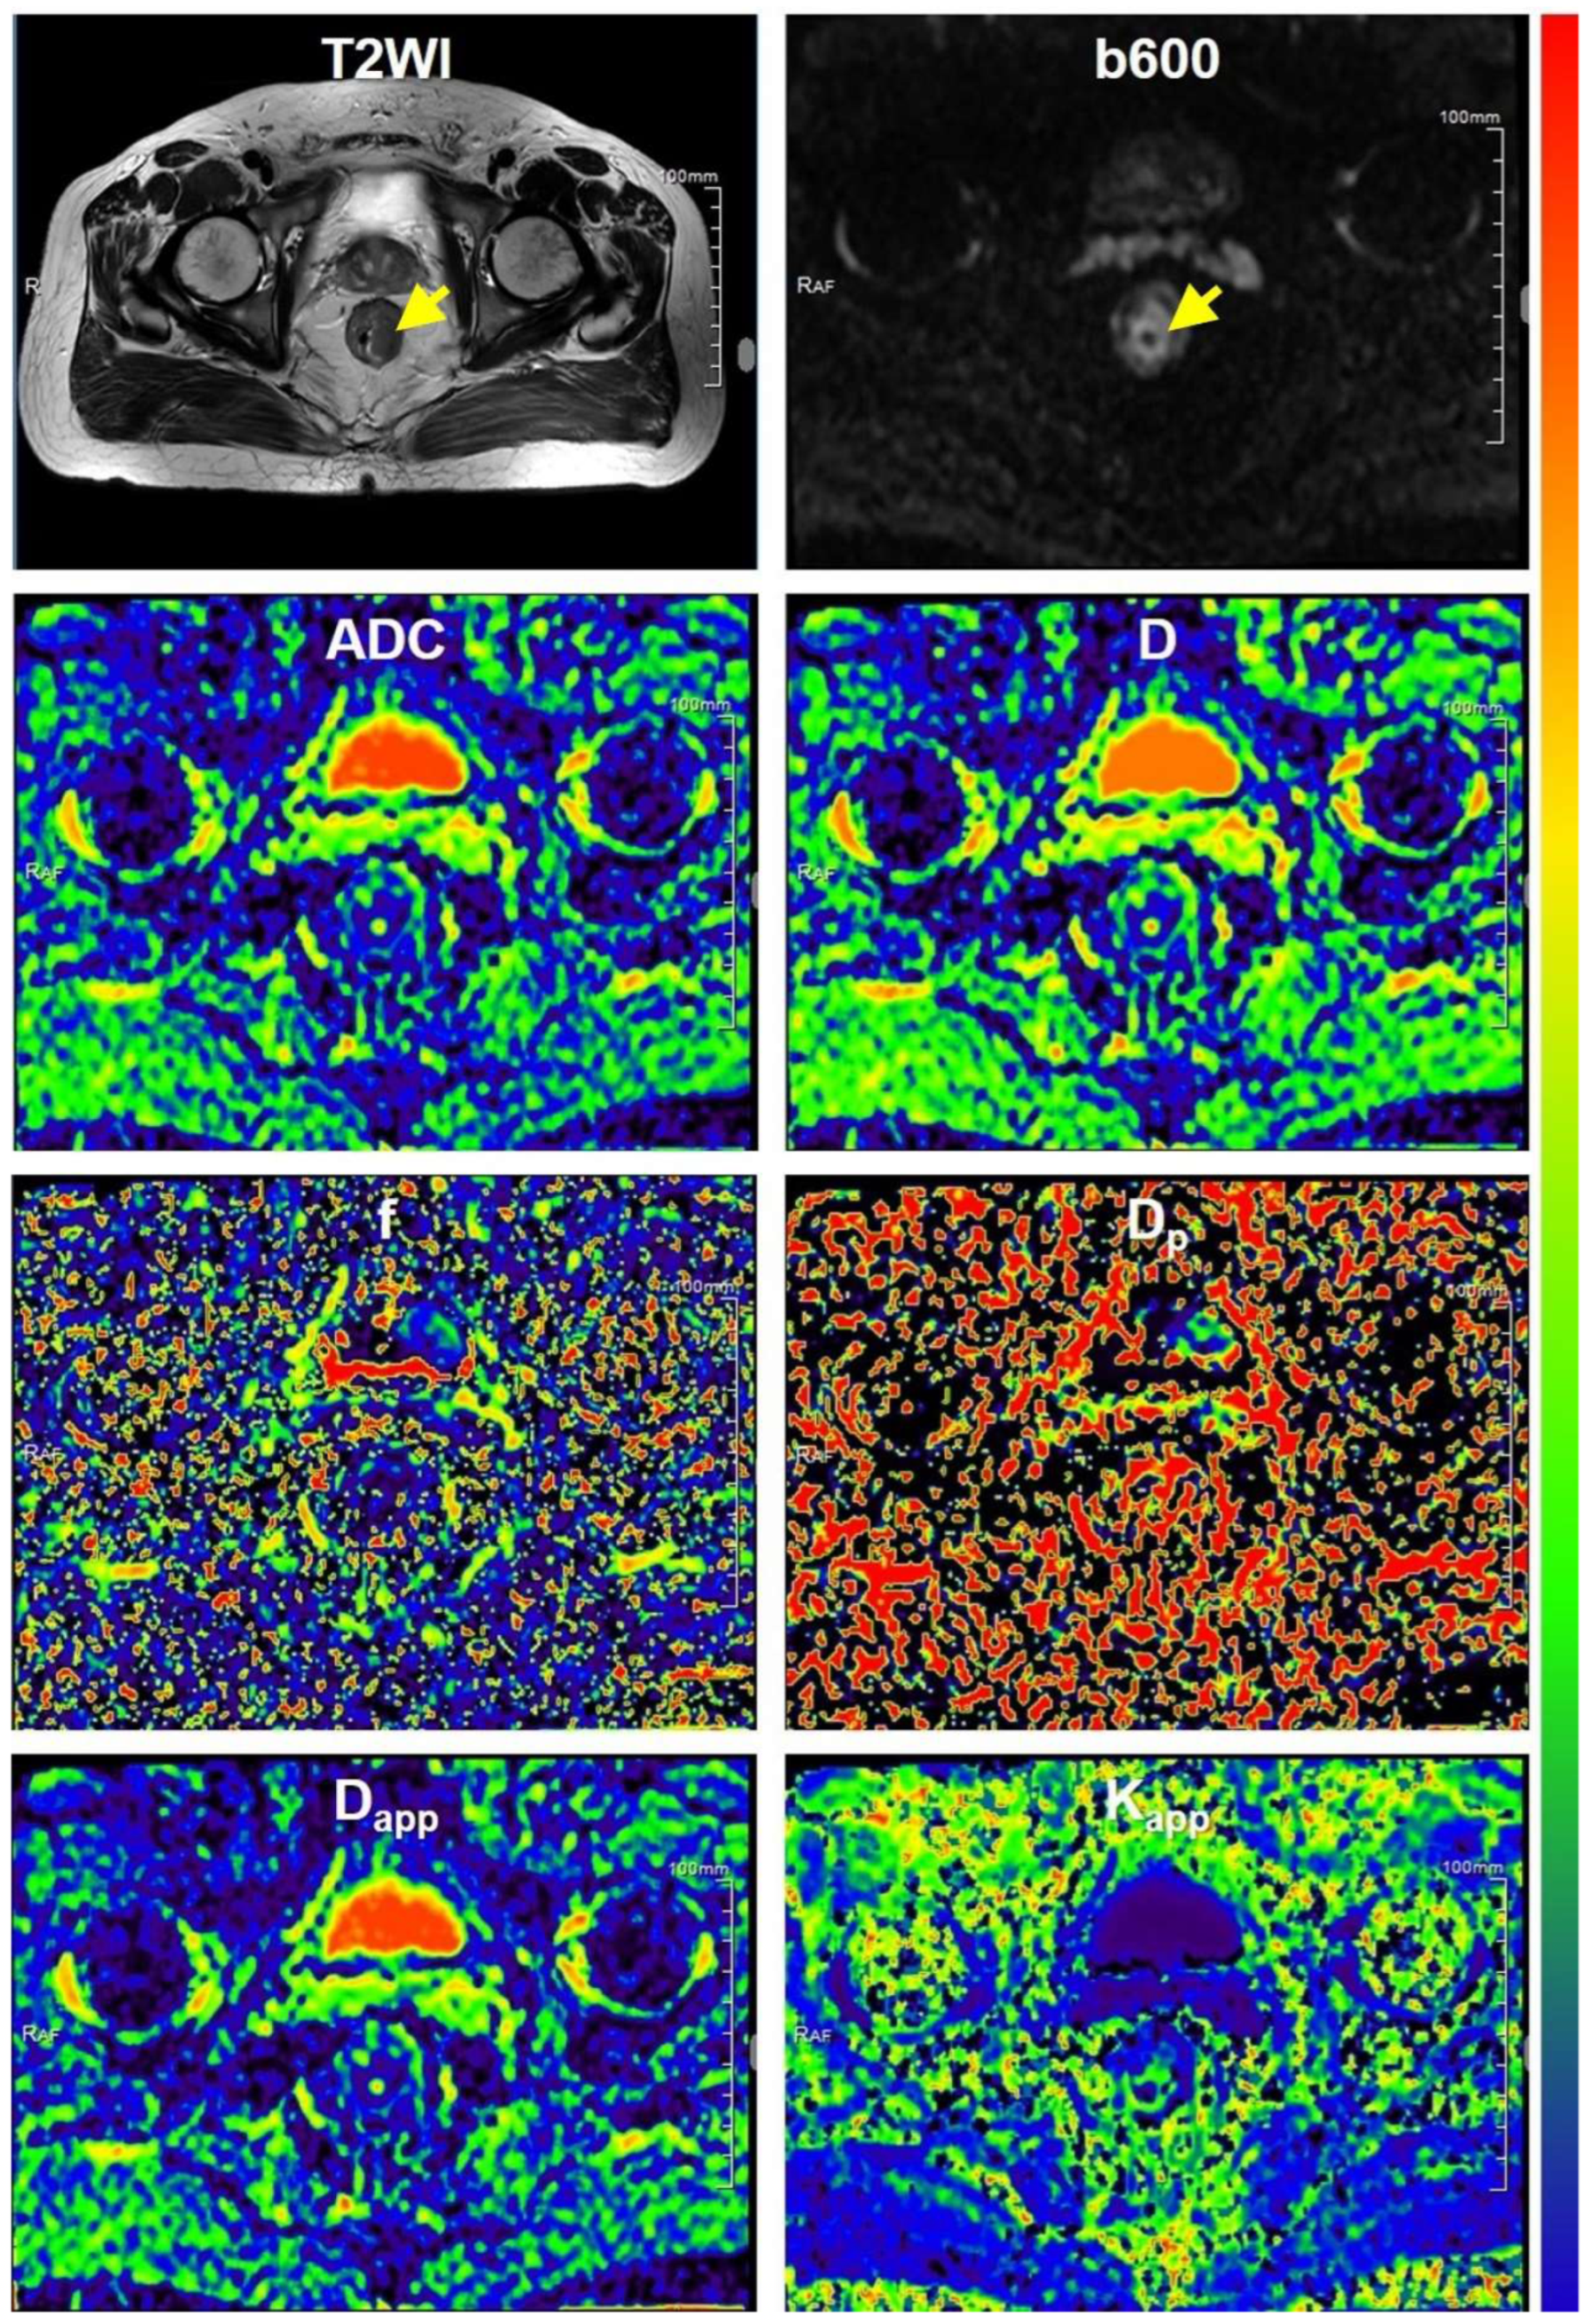

2.3.1. DWI Parametric Maps

3.1. Clinicopathological Characteristics and MR Images